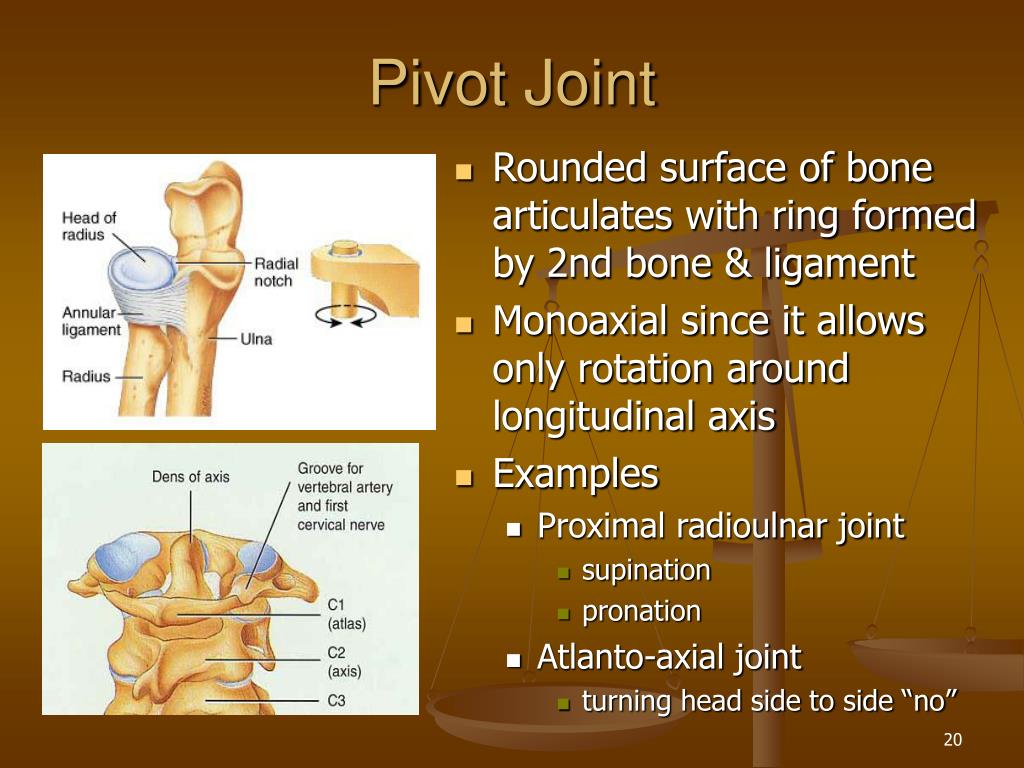

An example of a pivot joint is the atlantoaxial joint found between the C1 atlas and C2 axis vertebrae Here the upward projecting dens of the axis articulates with the inner aspect of the atlas where it is held in

Pivot joints are joints that allow bones to rotate In a pivot joint a cylinder shaped bone rotates inside another bone or ligament that forms a ring around it

An example of a pivot joint is the joint of the first and second vertebrae of the neck that allows the head to move back and forth Figure 4 The joint of the wrist that allows the palm of the hand to be turned up and down is also a pivot

A pivot joint is a synovial joint in which the ends of two bones meet one end being a central bony cylinder the other end being a ring or ring like structure made of bone and ligament In

A pivot joint in your neck lets your head move from one side to another Planar joints Planar joints are formed when two mostly flat bones come together They move by one

Pivot this joint can be found in the neck between the top two vertebrae It allows only rotational movement such as moving your head from side to side as if you were saying no

Pivot joints are joints that allow bones to rotate In a pivot joint a cylinder shaped bone rotates inside another bone or ligament that forms a ring around it

An example of a pivot joint is the atlantoaxial joint found between the C1 atlas and C2 axis vertebrae Here the upward projecting dens of the axis articulates with the inner aspect of the atlas where it is held in place by a ligament

Pivot joints are joints that allow bones to rotate In a pivot joint a cylinder shaped bone rotates inside another bone or ligament that forms a ring around it

An example of a pivot joint is the atlantoaxial joint found between the C1 atlas and C2 axis vertebrae Here the upward projecting dens of the axis articulates with the inner aspect of the atlas where it is held in place by a ligament